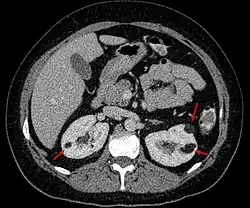

Coupe scanographique axiale montrant des angiomyolipomes sur les deux reins (flèches).

L'Angiomyolipome est une tumeur rénale bénigne constituée microscopiquement de vaisseaux, de muscles lisses et de graisse. Cette tumeur rénale est souvent de découverte fortuite de par sa croissance lente et sa relative innocuité, elle peut cependant être découverte à l'occasion d'hématurie ou d'hémorragies interne. Elle est associée dans 25 à 50 % des cas à une sclérose tubéreuse de Bourneville.

L'angiomyolipome est, dans la majorité des cas, une découverte de hasard lors d'un examen de l'abdomen par échographie, tomodensitométrie ou Imagerie par résonance magnétique.

• A la tomodensitométrie sans injection de produit de contraste il est de densité négative (UH<0, tonalité graisseuse) et se rehausse instantanément après injection (riche vascularisation).